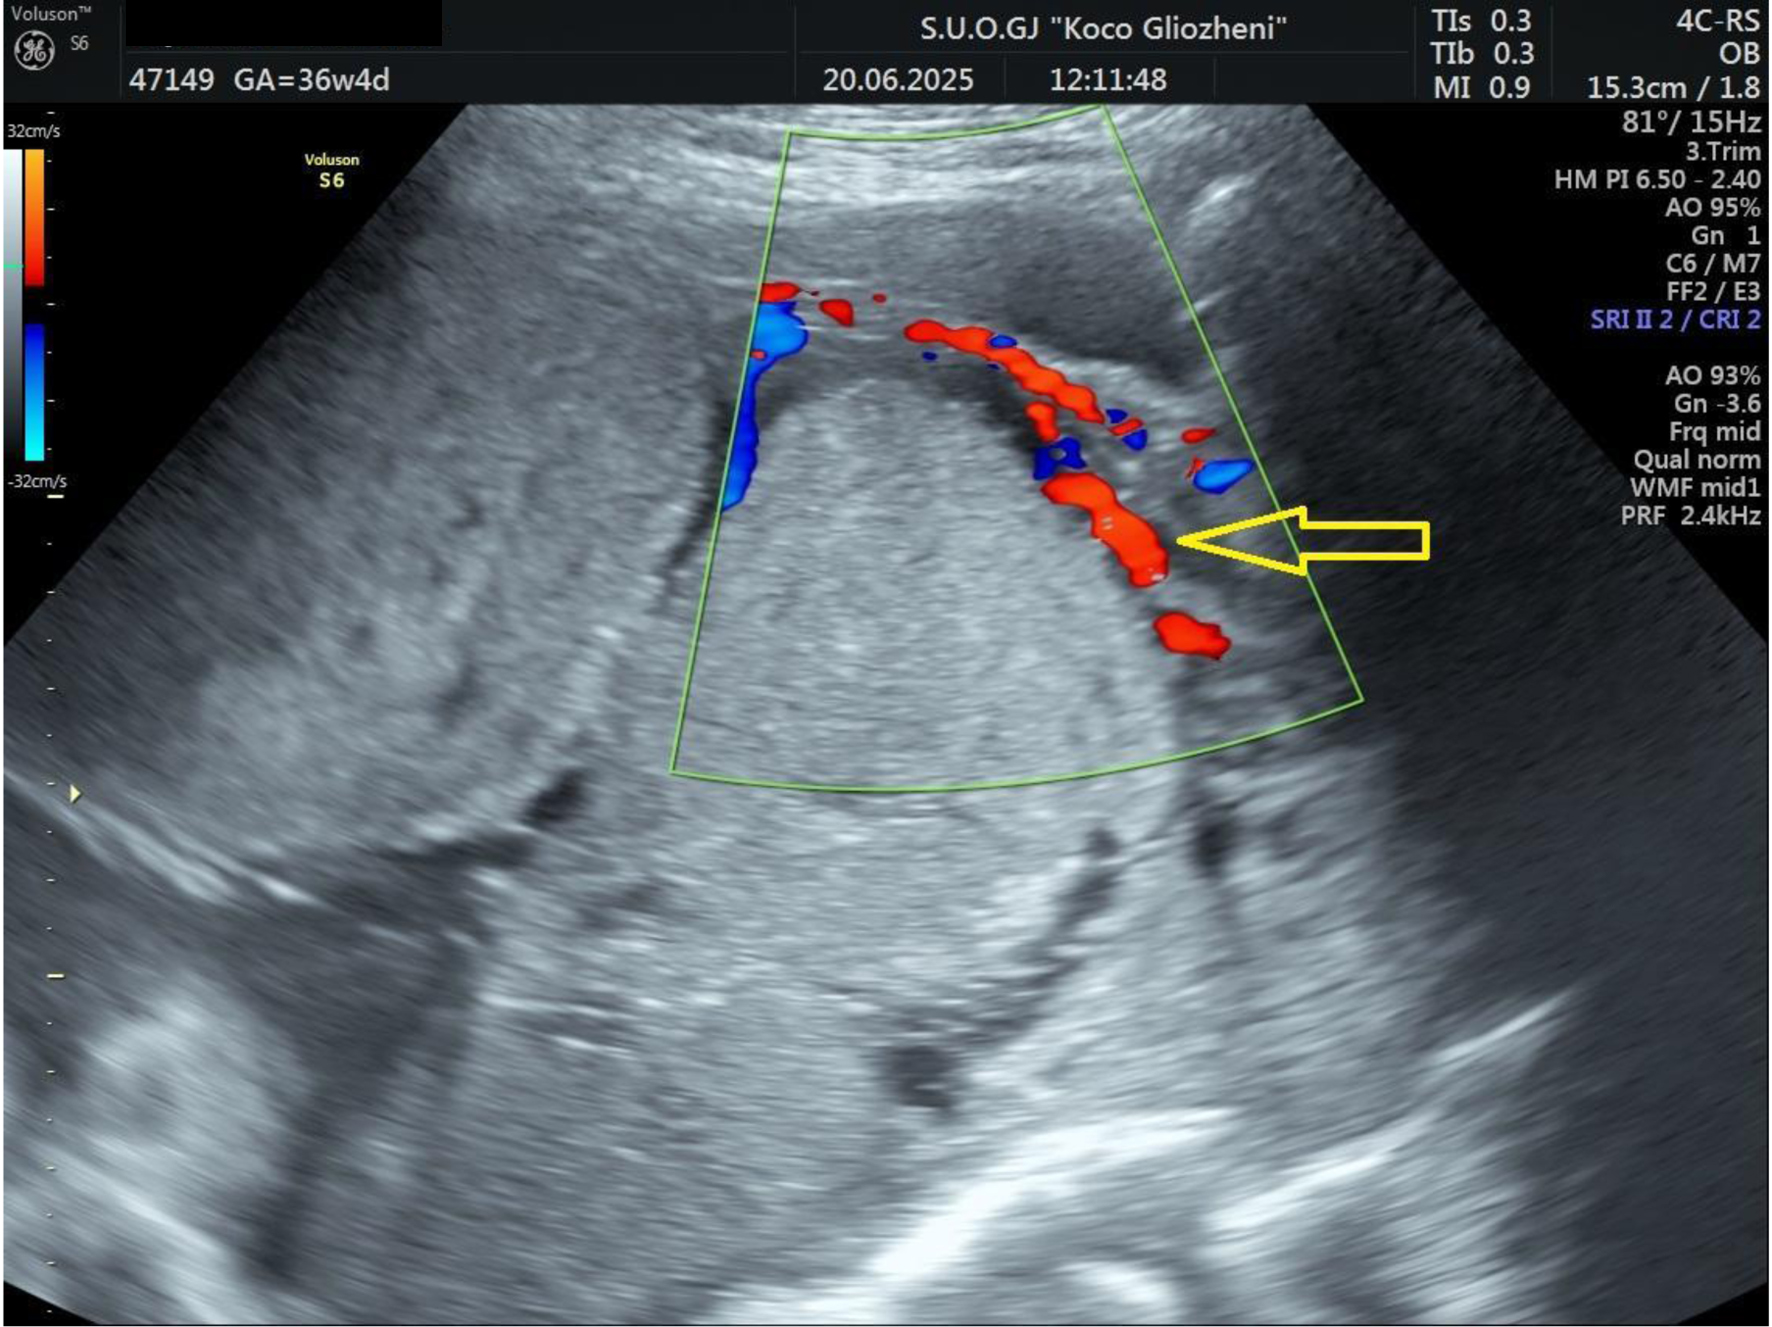

A 41-year-old woman at 36 - 37 weeks’ gestation, body mass index (BMI) 26 kg/m2, with a history of two prior cesarean deliveries and a transverse fetal lie, was admitted for evaluation. Ultrasound showed an anterior placenta completely covering the internal os, invading the full myometrial thickness up to the serosa, consistent with PAS, with marked Doppler vascularization (Figs. 1 and 2). So, elective cesarean section was indicated, and the blood bank was notified ensuring blood reserves. The surgical team was composed by obstetrician, vascular surgeon, and urologist.

Figure 1. Ultrasound examination showing placental tissue invading the lower myometrium (arrow).

Figure 2. Doppler ultrasound examination showing placental tissue invading the myometrium and extending to the serosa. Increased vascular flow was demonstrated on color Doppler ultrasound (arrow).